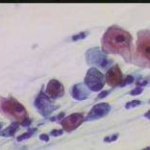

Κυτταρολογικές εικόνες προσβολής του τραχήλου της μήτρας από ιούς κονδυλωμάτων:

Κυτταρολογικές εικόνες προσβολής του τραχήλου της μήτρας από ιούς κονδυλωμάτων: Ασθενής 23 ετών, υποτροπές κολπίτιδος εναλλασσόμενης αιτιολογίας (κολπίτις μικροβιακής αιτιολογίας, κολπίτις από Candida albicans). Τώρα: pH 5, Στο νωπό παρασκεύασμα αρραιή μικροβιακή χλωρίδα. Κολποσκοπικώς επίπεδο μωσαϊκό στο πρόσθιο χείλος. Κοιλοκυττάρωση σε επιφανειακά και διάμεσα κύτταρα. Στην μικροβιοψία τραχηλίτις, υπόνοια για HPV.